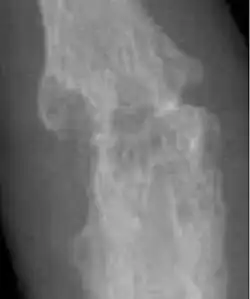

In the early stages of gout, usually only one joint is affected; however over time, many joints can become affected. Gout most commonly occurs in joints located in the big toe, knee, and/or fingers.[49] During a gout flare, the affected joints often become swollen with associated warmth and redness. The resulting pain can be significant and potentially debilitating.[71] When one of these flares occurs, management involves the use of anti-inflammatories, such as NSAIDs, colchicine, or glucocorticoids.[72] In between gout flares, it is recommended that patients take medications that decrease the production of uric acid (i.e. allopurinol, febuxostat) or increase the elimination of uric acid from the body (i.e. probenecid).[72][73]

Gout has been associated with excessive intake of alcohol and food, such as red meat.[49] Thus, it is also recommended that patients with gout adhere to a diet rich in fiber, vegetables, and whole grains, while limiting the intake of alcohol and fatty foods.[49]

There is also an uncommon form of gout that is known as pseudogout, which is caused by the formation of calcium pyrophosphate crystals in the joint.[74] Unlike gout, no targeted treatments are currently available.[74] At this time, management is aimed at decreasing inflammation in order to reduce the intensity and frequency of flares.[74]